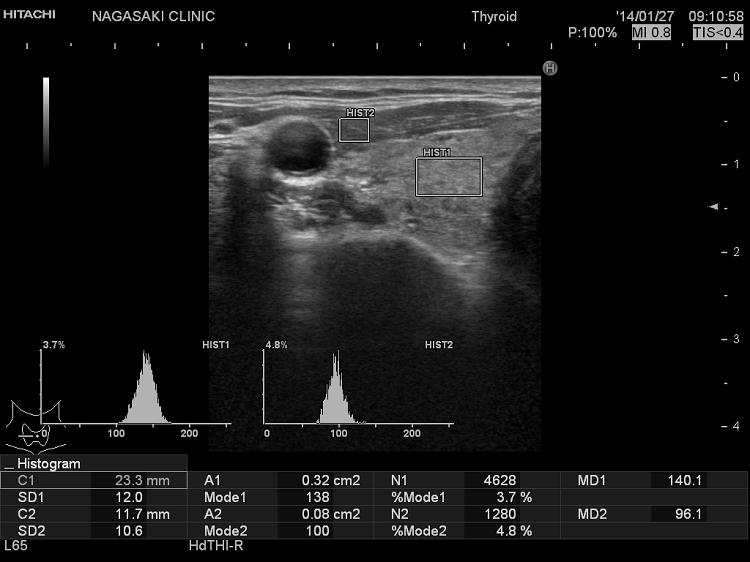

グレースケール解析(甲状腺内部の新たな評価法)

橋本病(慢性甲状腺炎)において、超音波(エコー)検査で評価した甲状腺のエコー輝度(白さと黒さの度合い)は、甲状腺内部の炎症と破壊の程度やホルモン産生能を総合的に反映します。特に甲状腺機能低下症では、甲状腺ホルモン(FT4)や甲状腺刺激ホルモン(TSH)値と有意に相関します。

甲状腺機能亢進症/バセドウ病において、超音波(エコー)検査で評価した甲状腺のエコー輝度(白さと黒さの度合い)は、バセドウ病の活動性を反映します。バセドウ抗体(TRAb)が高値な程、TSH抑制されている程、甲状腺のエコー輝度は低くなります。(European Journal of Endocrinology (1999) 141 332–336)。

グレイスケール解析

甲状腺機能低下症 正常人

甲状腺のエコー輝度(GWE) 61·9 ± 8·3 71·9 ± 3·1

バセドウ病 正常人

甲状腺のエコー輝度(GWE) 21.3 ± 3.3 25.6 ± 2.0

甲状腺のエコー輝度(GWE)は、超音波(エコー)機械によってかなりばらつきがあります。超音波(エコー)機械毎の正常値の設定が必要になります。